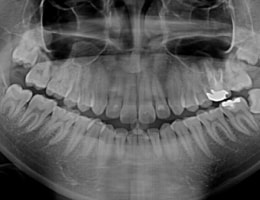

被曝量の少ない「デジタルレントゲン」を完備!

超高感度だから被曝量が軽減!子供さんにも優しいレントゲン!

デジタルレントゲンに使われているX線センサーは、デジタルならではの高感度!

照射時間が短縮され、より低線量でのレントゲン画像取得が可能となります。

また、各ユニットのデジタルモニターにも直接映像を映し出すことが出来るため、

当院のデジタルレントゲンは、

従来のフィルムを使用したレントゲン撮影に比べ、

人体に受ける放射線の量を、約1/4~1/10に抑える事が可能です。

照射時間がかなり短く、安心安全です。

大きなパノラマレントゲンは歯並びなど、全体像をつかむことにも有効的ですが、

現状を詳細に把握するため、小さいレントゲンを10枚撮って診断・治療をしております。

これにより歯石、歯周ポケット等も詳細に把握でき、緻密な治療を提供することが出来ます。